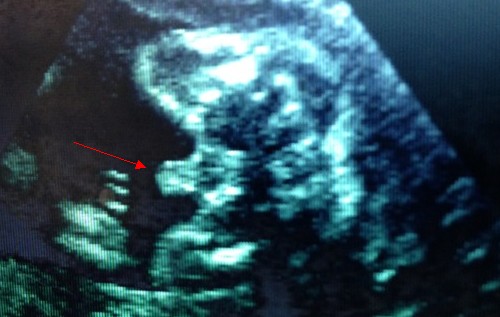

直接B超看性別,簡(jiǎn)單粗暴準(zhǔn)確率高。請(qǐng)大家不要糾結(jié)不給B超看男女國(guó)情好嗎?咱中國(guó)人辣么聰明,想做的事情有什么辦不到的呢?

23周男寶B超圖,小jj辣么明顯。

但是偶爾也會(huì)有翻盤(pán)的時(shí)候(B超是女,生下來(lái)是男?;蛘邉偤孟喾矗?,準(zhǔn)確率95%。